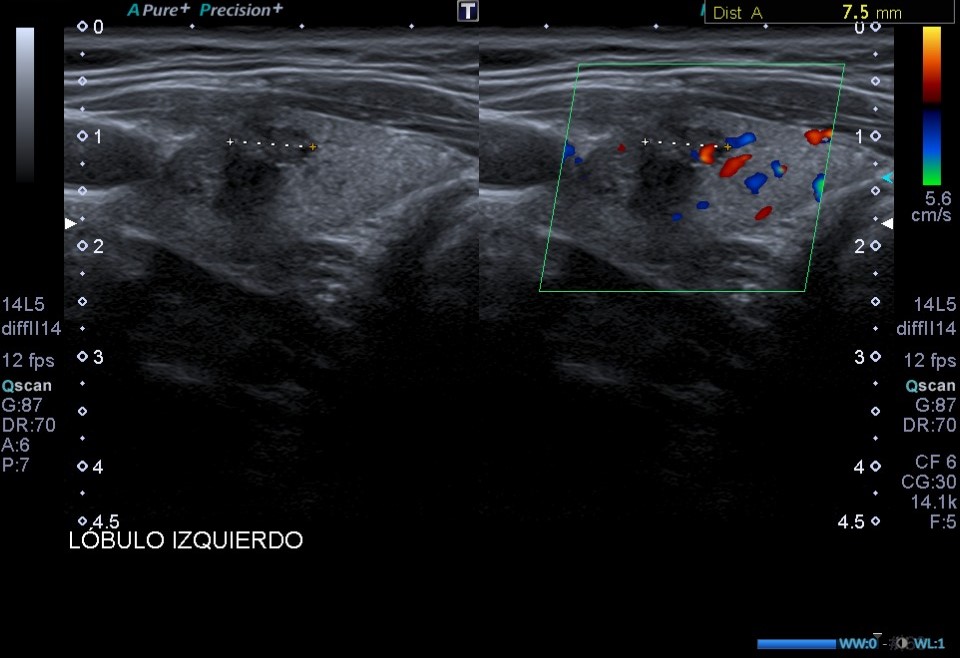

Ecografía de tiroides en consulta: En el LTI presenta dos lesiones nodulares en el área central del lóbulo tiroideo, presentando ambas un aspecto heterogéneo, bordes y márgenes mal definidos y microcalcificaciones.

Dada la presencia de nódulos tiroides con patrones ecográficos de alta sospecha de malignidad (bordes y márgenes mal definidos y presencia de microcalcificaciones), se solicita ecografía tiroidea reglada, y derivar a especialista en función de resultados.